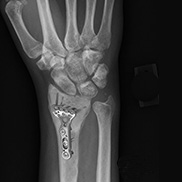

Open reduction and internal fixation of the wrist is a surgical technique employed for the treatment of severe wrist fractures to restore normal anatomy and improve range of motion and function.

Open reduction and internal fixation is the procedure employed most often to treat displaced wrist fractures.

- The fragments of bone are then held in place with wires, screws, pins, or metal plates attached to the outer surface of the bone.

Depending on your health condition and the extent of the injury, you may be able to go home the same day with scheduled follow-up appointments for monitoring progress and for stitches or staple removal if necessary. Your doctor will order X-rays to monitor healing throughout your treatment. Most people return to their normal activities within a couple of months.